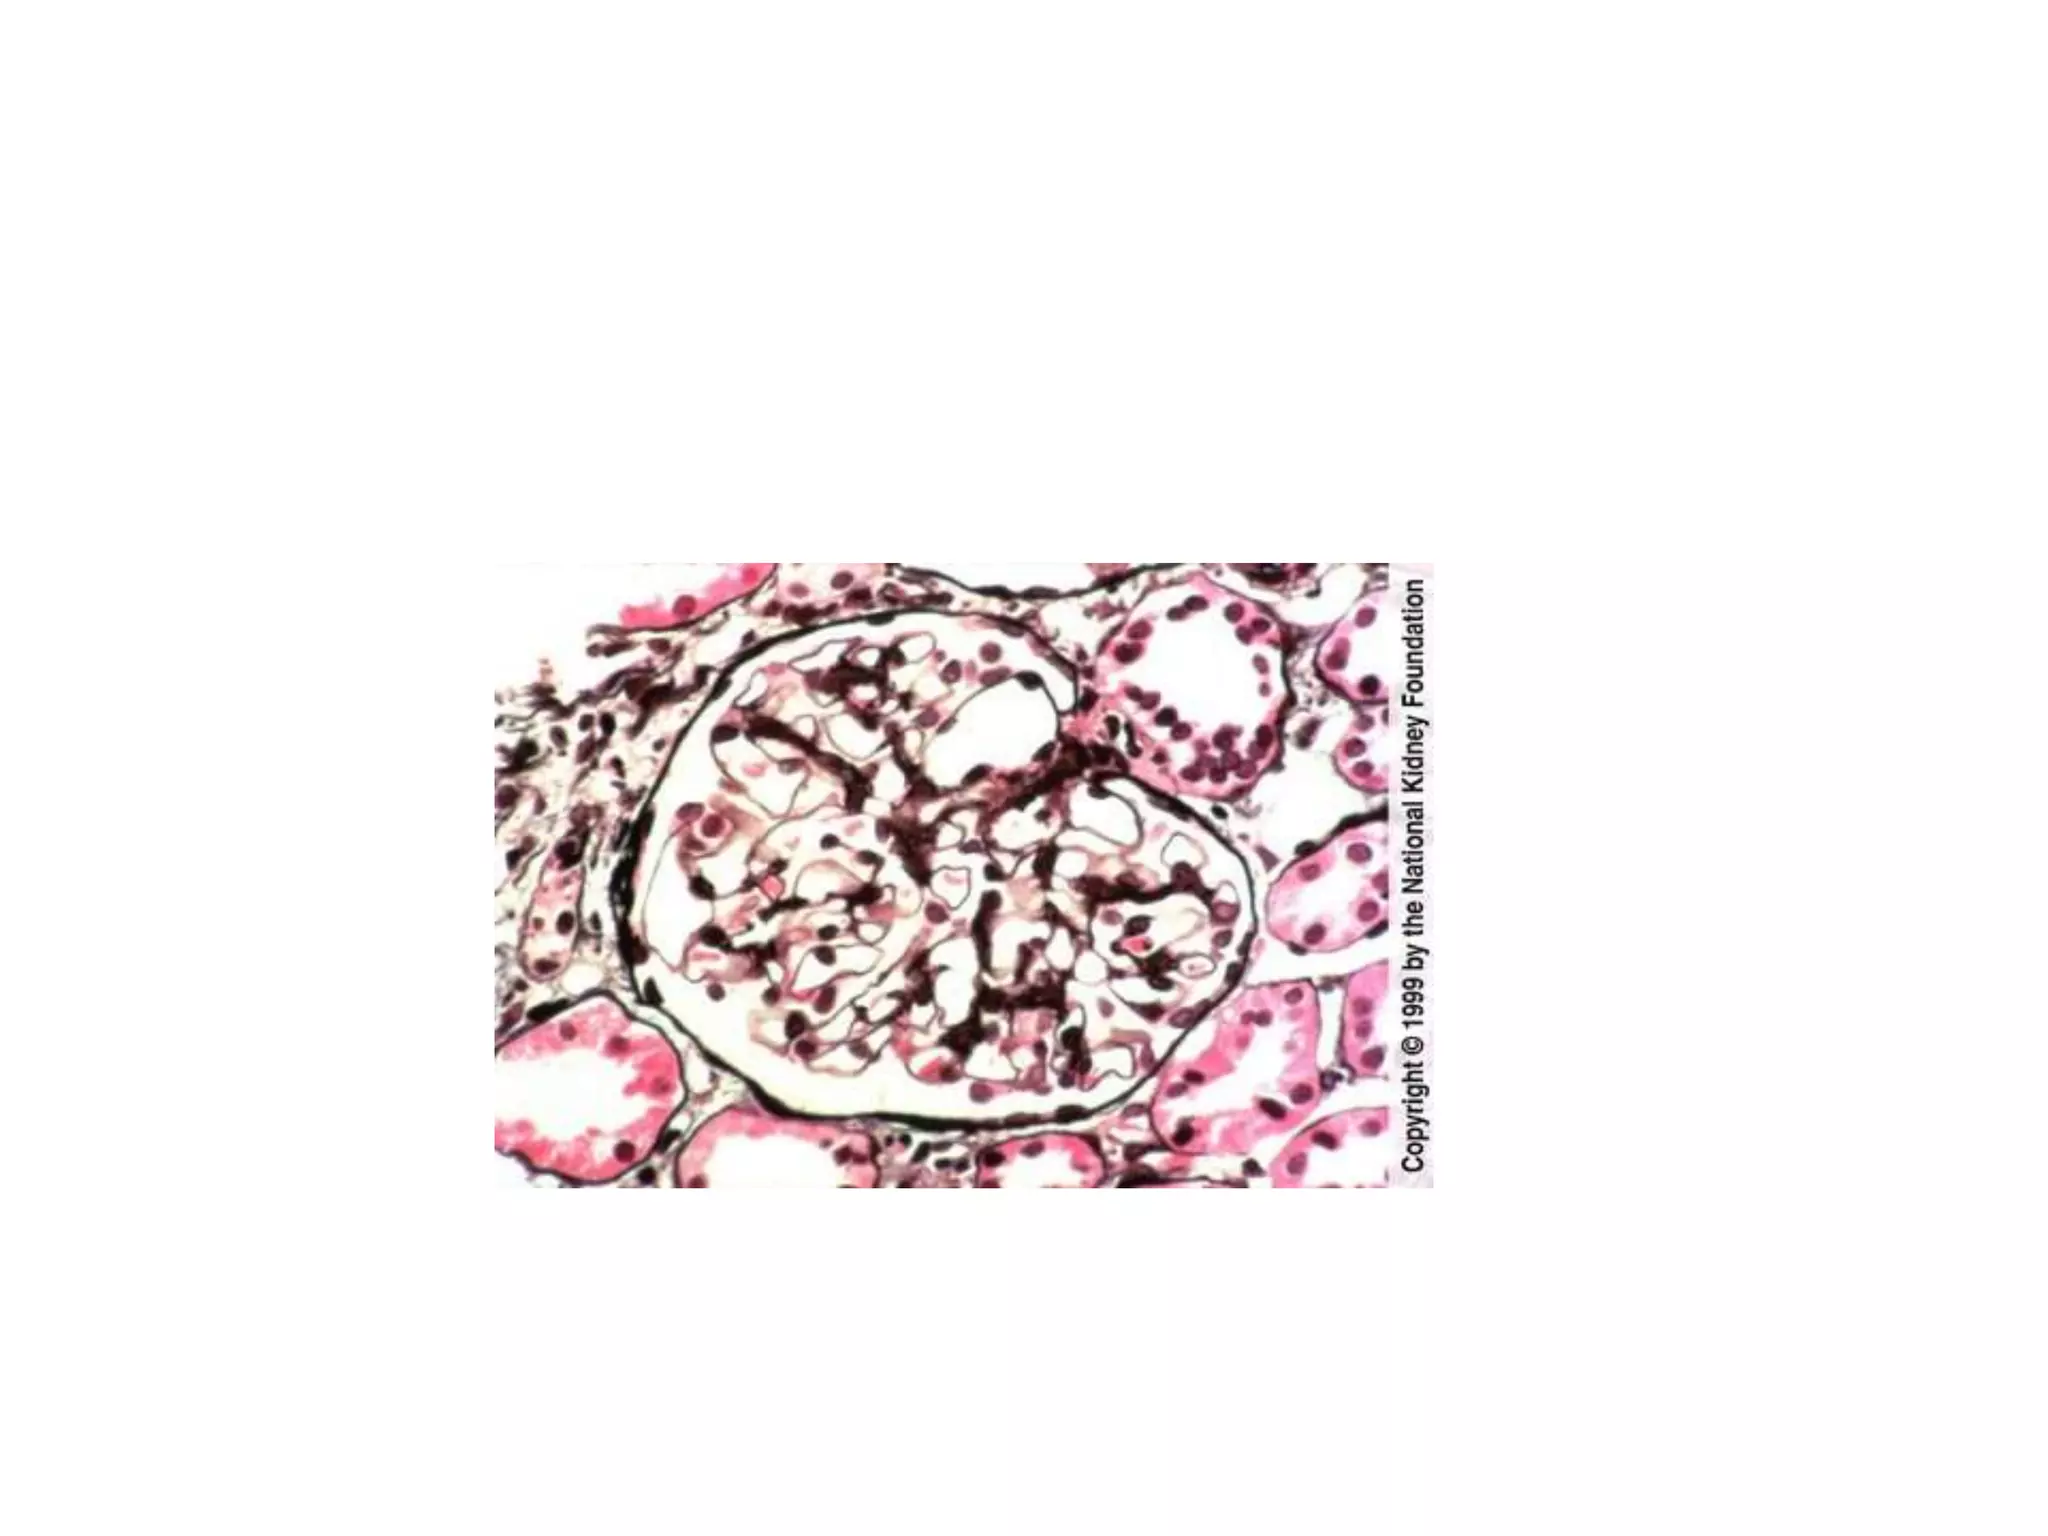

Review of the biopsy specimen

• Glomerulus: Diffuse/focal. Segmental/global.

• Endothelium, glomerular basement

membrane, podocyte, mesangium (cells and

matrix), urinary space, Bowman’s capsule.

Review of thebiopsy specimen • Glomerulus: Diffuse/focal. Segmental/global. • Endothelium, glomerular basement membrane, podocyte, mesangium (cells and matrix), urinary space, Bowman’s capsule. • Interstitium: Tubules, casts, fibrosis, inflammatory infiltrate, arterioles • Light, immunofluorescence, and electron microscopy constitute a full biopsy